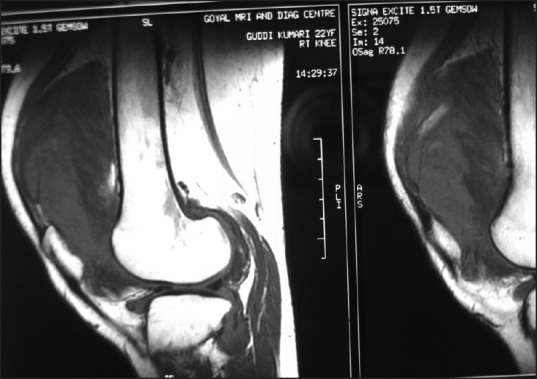

Figure 2.

Sagittal magnetic resonance imaging of the left knee. The presence of a multiple nodular mass and low signal intensities indicating hemosiderin deposit were diagnostic of diffuse pigmented villonodular synovitis

A 21-year-old female presented to the Outpatient Department(OPD) of our hospital located in New Delhi, India, with insidious onset pain and swelling in her right knee joint for the past eight months. There was no specific history of trauma. She was initially treated with non-steroidal anti-inflammatory drugs (NSAID) by her general physician. Subsequently, open subtotal synovectomy was done at a different institution. This provided slight improvement in the symptoms for some time, but they did not subside completely and she was referred to our hospital. Initial examination revealed moderate diffuse swelling and pain around the knee joint with mild increase in local temperature, but with no definite erythema or fever. The joint swelling was disproportionate to the amount of pain. Her range of knee motion was 30-100°, and quadriceps atrophy was prominent. Diagnostic arthrocentesis revealed bloody colored fluid containing 590/mm3 white blood cells, with 70% being polymorphonuclear cells. Blood tests showed a leukocyte count of 7200/cmm and an erythrocyte sedimentation rate (ESR) of 20 mm/hour. Plain anteroposterior and lateral radiographs of the right knee joint revealed no bony or soft tissue abnormality [Figure 1]. Magnetic resonance imaging (MRI) revealed diffuse synovitis with synovial proliferation. A multiple nodular mass was observed in the infrapatellar fat pad and suprapatellar region [Figure 2]. Bony erosion was prominent around the posterior horn of the medial meniscus. T1- and T2-weighted images showed low-signal intensity, indicative of clumps of hemosiderin deposits, diagnostic of PVNS. The combination of hemosiderin deposits and a nodular soft tissue mass around knee joint on MRI was highly suggestive of PVNS. Additionally, as there were no clinical or radiological signs of tuberculosis, it was not suspected. Chest radiographs of the patient revealed no active or past signs of tuberculosis. She was, therefore, diagnosed with PVNS of diffuse type. An arthroscopic approach was chosen to do synovectomy, for excision of diffuse PVNS. The intraoperative aspirate revealed a bloody aspirate suggestive of the possibility of PVNS [Figure 3]. Arthroscopic examination showed marked diffuse synovitis between the infrapatellar fat pad and anterior cruciate ligament (ACL). A histological examination of the tissue showed necrotizing granulomatous inflammation, highly suggestive of mycobacterial infection [Figure 4]. No villi form synovial proliferation or pigmented multinucleated giant cells with hemosiderin-laden macrophages were observed. Anti-TB drugs were prescribed and the patient completed 12 months of pharmacotherapy at the following doses: Isoniazid 300 mg OD, Rifampicin 600 mg OD, Pyrazinamide 1500 mg OD, Ethambutol 1000 mg OD, and Pyridoxine 10 mg OD. Synovial culture was eventually positive for Mycobacterium tuberculosis. The patient completed an uneventful 12-month course of anti-tuberculous chemotherapy without radiological evidence of tuberculosis progression, such as, joint space narrowing, juxta-articular osteopenia or erosion. At follow-up 20 months later, she was free of pain and had regained full range of knee motion.

Many physicians confronted with patients presenting with chronic unilateral knee arthritis of unknown origin should include tuberculous knee arthritis in the differential diagnosis, so as to avoid misdiagnosing patients with this condition, with having other inflammatory or neoplastic processes with similar clinicoradiological characteristics, such as PVNS. Tuberculous arthritis in a young, immunocompetent patient is especially rare, making such a diagnosis difficult. An improper diagnosis may be due to atypical clinical presentation, wide use of antibiotics, low specificity of diagnostic tools, and most of all, the clinician not suspecting the possibility of tuberculous arthritis, due to its varied clinical presentations mimicking another pathology. An analysis of 10 patients with tuberculous knee arthritis, diagnosed preoperatively by clinical and radiological examination, including MRI and polymerase chain reaction (PCR) assays, found that only 2[2] (20%) were properly diagnosed at admission, whereas, the other eight (80%) were misdiagnosed preoperatively with rheumatic arthritis, gouty arthritis or osteoarthritis.[9] Furthermore, the patient described here was initially suspected to have diffuse PVNS, because of her clinical manifestations and MRI features. Both tuberculous arthritis and PVNS in the knee joint of young, otherwise healthy-appearing individuals may present as monoarticular involvement, with painful swelling of long duration (usually more than several months to years) and limited motion. On MRI, both conditions show synovial proliferation, reactive bone marrow edema, and cortical erosion. Moreover, clumps of hemosiderin deposits on T1- and/or T2-weighted MRI are more indicative of PVNS than of tuberculous arthritis.[10]